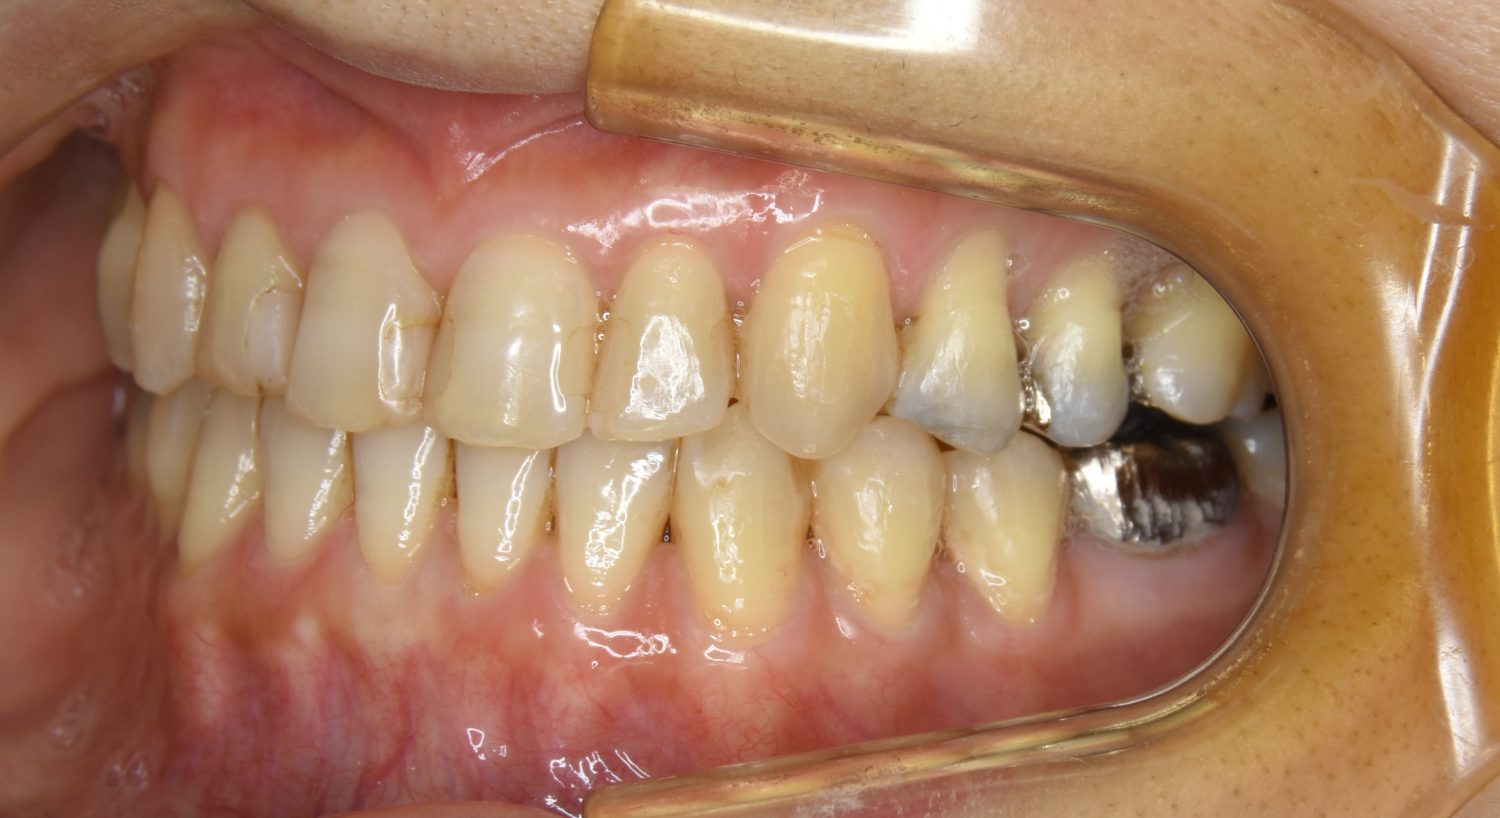

叢生の症例紹介②

Before

After

主訴

歯の凸凹を治したい。

治療内容

アライナー(インビザライン)にて非抜歯で治療を行いました。

上下前歯部に叢生(凸凹)が認められる状態でした。歯列の遠心移動を行うことで機能面および審美面が改善されました。